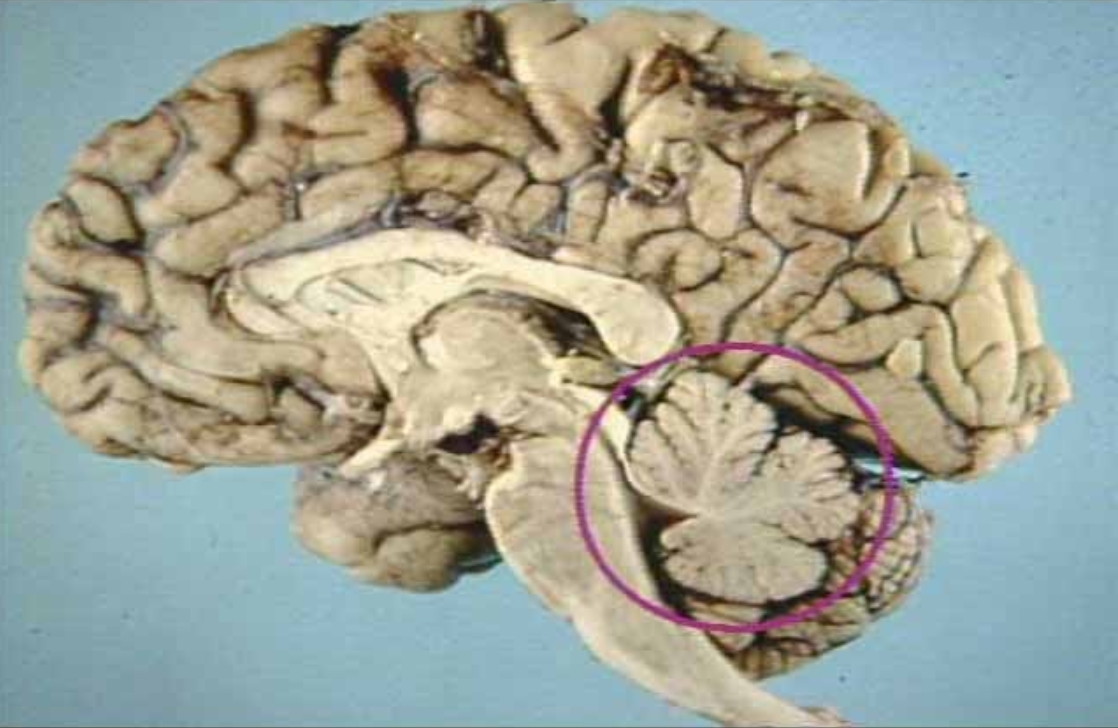

What is in the circle?

Cerebellum